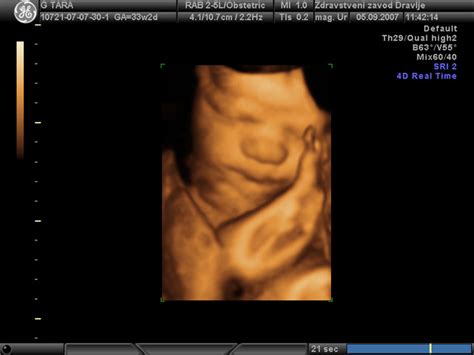

Nuhalna svetlina je v bistvu majhna količina tekočine, ki se nabira v podkožju v predelu zatilja ploda v prvem trimesečju nosečnosti. Ta tekočina je normalno prisotna pri vseh plodovih v tej razvojni fazi. Pri meritvi nuhalne svetline, ki jo strokovno imenujemo tudi presejanje za kromosomopatije, ultrazvočni tehnik z visoko frekvenco zvočnih valov ustvari slike otroka v maternici in izmeri debelino tega tekočinskega prostora. Na ultrazvočni sliki se nuhalna svetlina običajno prikaže kot temno območje na zadnji strani plodovega vratu.

Optimalni čas za izvedbo meritve nuhalne svetline je med 11. tednom nosečnosti (ko je dolžina ploda približno 45 mm) in 13. tednom ter 6 dnevi (ko je dolžina ploda približno 84 mm). V tem časovnem okviru je razvoj ploda dovolj napredoval, da je mogoče zanesljivo izmeriti tekočino za vratom. Prej ali kasneje opravljene meritve niso tako zanesljive in so lahko nejasne ali nerelevantne.